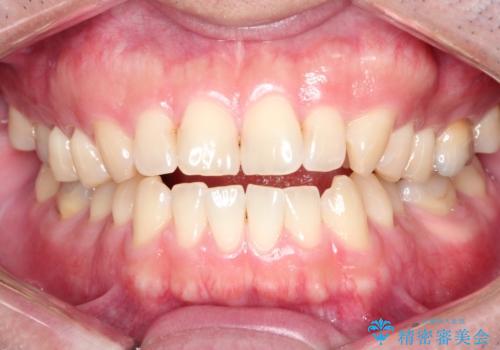

奥歯の噛み合わせは整っていたため、前歯の並びを美しく修正することに専念できました。マウスピース矯正による治療で短期間で改善しました。

前歯のガタツキを改善する治療法として、マウスピース矯正が適していることが多いです。

マウスピース矯正は、金属製のブラケットやワイヤーを使用せずに、透明なマウスピースを装着して歯を移動させる方法です。そのため、目立たず、痛みも少ないです。